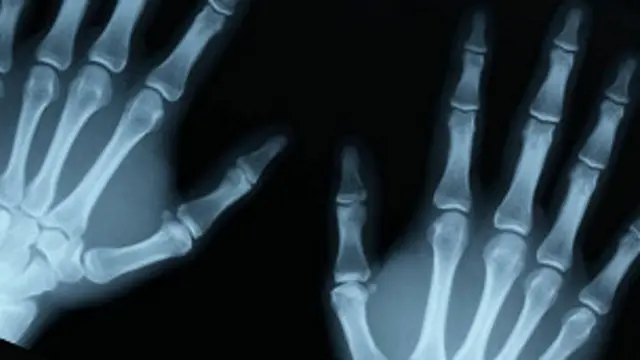

Una impresora 3D ha comenzado a ser utilizada para crear huesos a partir de un material muy similar al tejido óseo, el cual según los investigadores serviría para reparar lesiones.

Los ingenieros dicen que la sustancia se puede añadir al hueso natural dañado y actuar como un andamio para hacer crecer nuevas células

El hueso dañado es reproducido en su forma original mediante la impresión de capas sucesivas.

La superposición de estas múltiples capas la mitad de delgadas de un cabello humano es lo que permite reproducir la forma y la arquitectura interna del hueso con precisión.